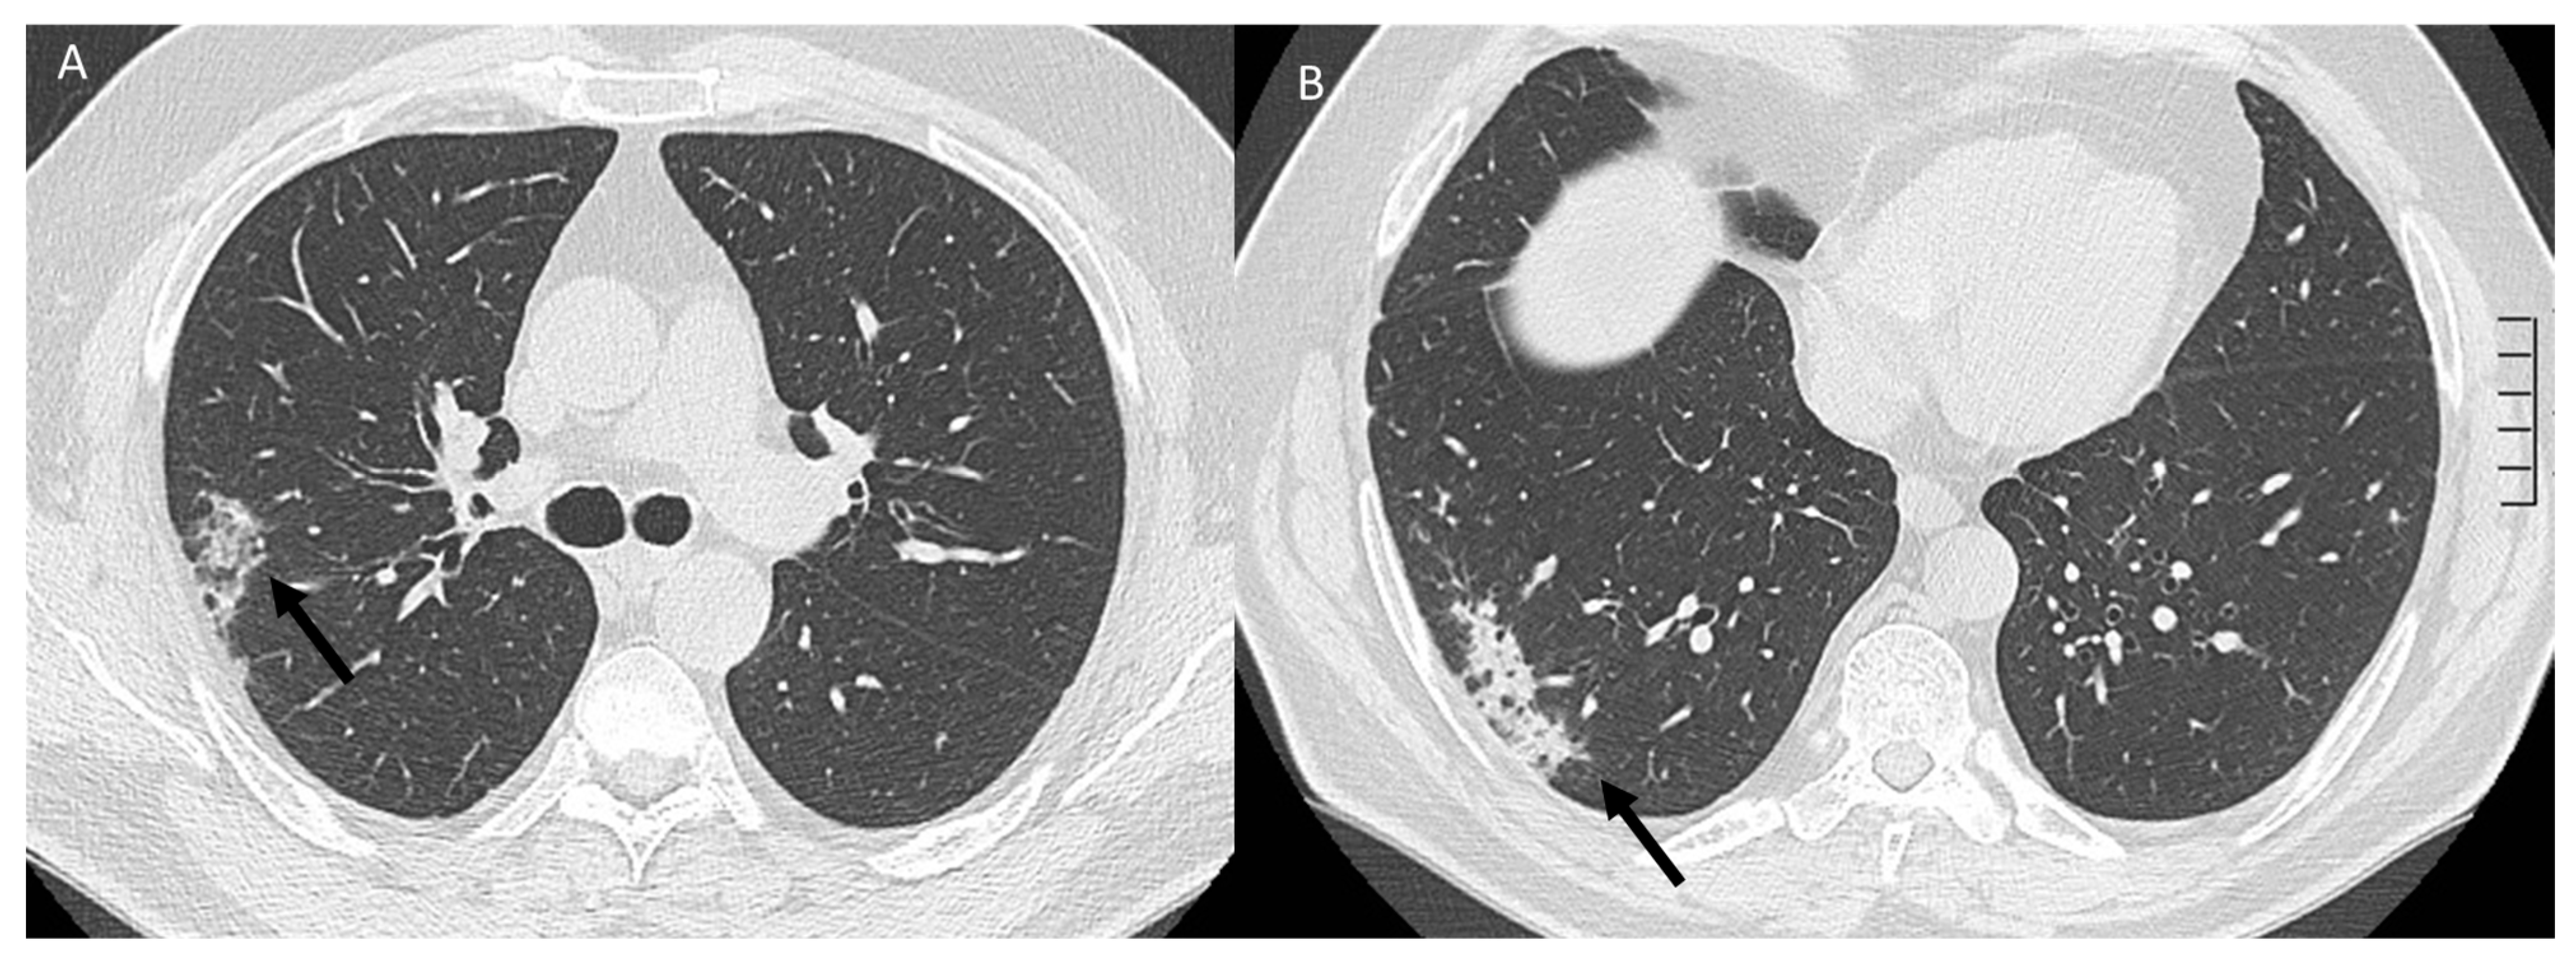

| ICI-related pneumonitis | Diffuse (related to the phase of disease) | Ground-glass and reticular opacities; consolidative opacities; interlobular septal thickening; “crazy-paving” pattern | Autoimmune |